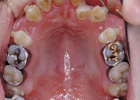

歯を抜いて治療した例 その2

治療前

治療後